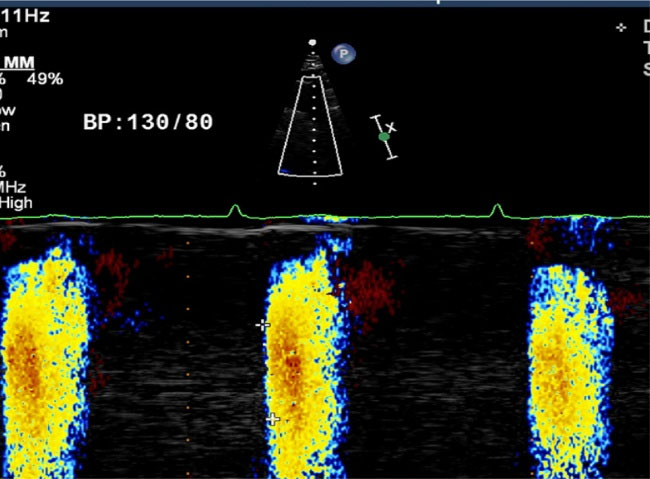

Measurement of AVP

The patient is kept in a supine position with neck extension and from suprasternal view, colour M-mode Doppler recordings were recorded from the proximal descending thoracic aorta (DTA) and the cursor was put parallel to the main flow of direction in the proximal DTA. Color Doppler Nyquist limit and m-mode recorder sweep rate was kept between 30–50 cm/s and switched to M-mode with a recorder sweep rate of 200 mm/s; an M-mode spatiotemporal velocity map in the shape of a flame was displayed. The aortic flow propagation velocity was then measured in cm/s by tracing the velocity slope (). Beginning and end point of the propagation slope was taken into the calculation. AVP corresponds to the velocity at which the flow was propagating down the artery. The average of 3 measurements was recorded as the AVP value. Intra-observer and inter observer variations were less than 10% which were not significant for APV measurement.

jcvtr-14-153-g001

Figure 1. Measurement of AVP.